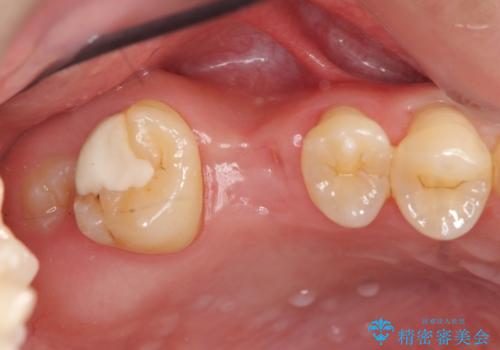

ソケットリフトを伴うインプラント補綴

- 右上の歯を喪失し機能回復を希望され来院されました。

骨量が不十分であった為、ソケットリフトを併用しインプラントによる補綴計画を立てます。